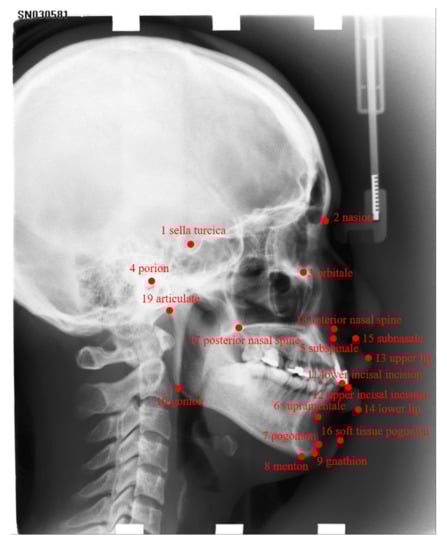

We aim to detect 19 landmarks for each X-ray image, as presented in Figure 1, which are as follows: sella turcica, nasion, orbitale, porion, subspinale, supramentale, pogonion, menton, gnathion, gonion, lower incisal incision, upper incisal incision, upper lip, lower lip, subnasale, soft tissue pogonion, posterior nasal spine, anterior nasal spine, and articulate.

Figure 1. All 19 landmarks on x-ray images which we aim to detect.